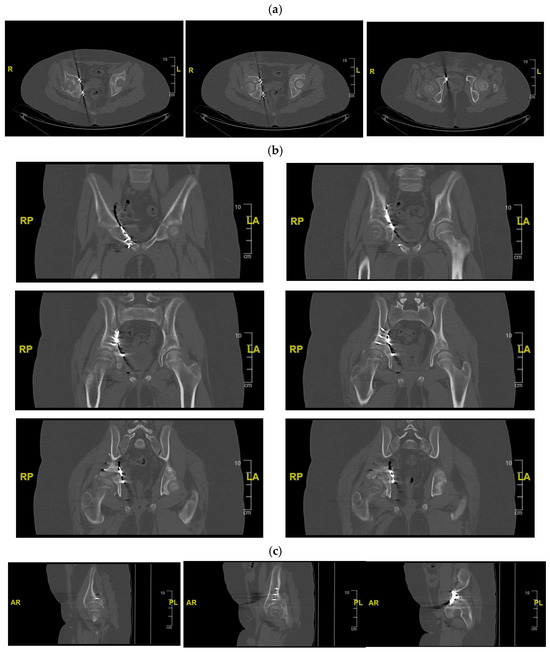

Figure 3.

CT of the pelvis showing the right acetabular fracture. (a) Axial view; (b) sagittal view; (c) coronal view. R = right; L = left; A = anterior; P = posterior.

Initial radiographs (Figure 2) and CT imaging revealed an open fracture of the right tibia with involvement of the tibial plateau (Schatzker IV) and a vertical fracture line extending below the tibial tuberosity; a transverse fracture of the right acetabulum with disarticulation of the triradiate cartilage (Figure 3); a suspected fracture at the level of the left lesser trochanter; bilateral pulmonary contusions (segments of the upper and lower lobes); a thin parafalcine and paratentorial intracranial haemorrhage without mass effect; no craniofacial or cervical spine fractures; no solid-organ injury in the abdomen; a small simple cyst in the left kidney; and developmental changes in thoracic vertebral bodies (D6–D8) without acute traumatic lesions. The patient was haemodynamically stable after initial resuscitation. Neurovascular examination of the lower limbs was normal at presentation.

Definitive management of the acetabular fracture was deferred until the patient’s general condition was optimised and soft-tissue status allowed surgery. A CT scan with multiplanar and 3D reconstructions of the pelvis confirmed a transverse acetabular fracture involving the triradiate cartilage on the right side, with displacement of the quadrilateral surface and medialisation of the femoral head relative to the hemipelvis.